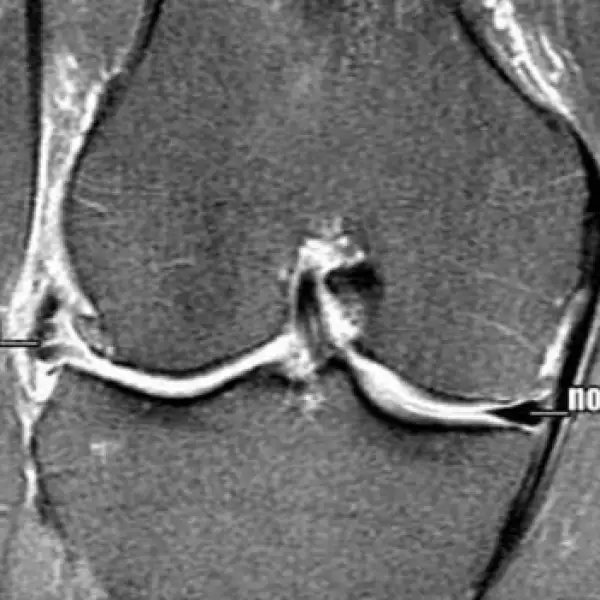

Cuidado con las rodillas, signo de peligro para el golfista promedio

La lesión que marginó a Tiger Woods de durante casi tres meses es un problema común en el golf